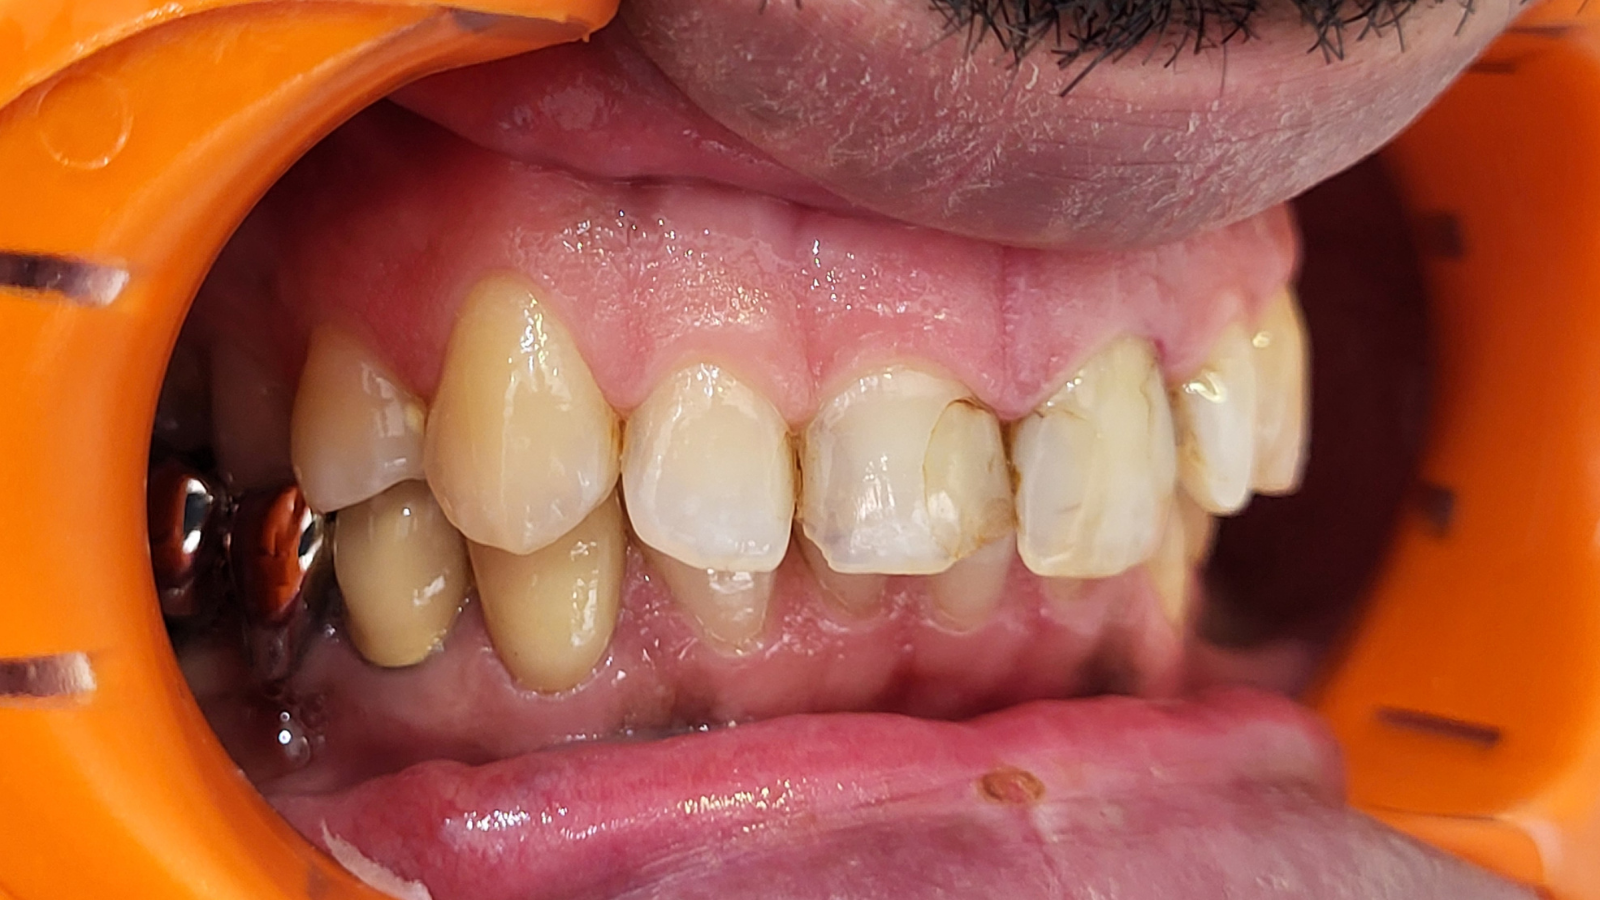

Facettes de canine à canine : sourire plus harmonieux et naturel

Un patient se présente pour rendre son sourire plus harmonieux. Les images “Avant” montrent un secteur antérieur avec une esthétique perfectible, notamment au niveau de l’homogénéité, des contours et du rendu de surface.

La prise en charge a consisté en des facettes de canine à canine, avec un objectif clair : retrouver un résultat naturel avec de la brillance, du relief et de la translucidité.

Les images “Après” mettent en évidence un sourire plus équilibré, avec une meilleure continuité entre les dents, un rendu plus lumineux et une texture plus réaliste.